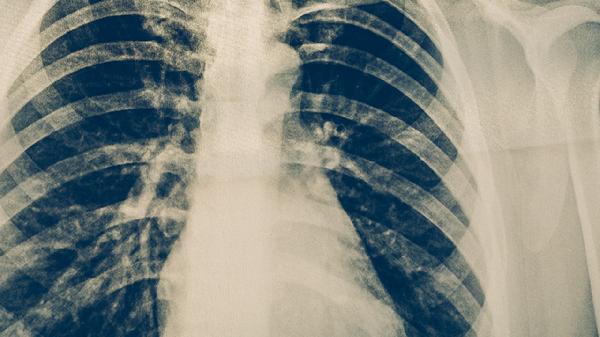

肺炎有哪些类型

肺炎主要分为五种类型:细菌性、病毒性、支原体性、真菌性和吸入性。每种类型的病因、表现和治疗方法各有不同,因此需要根据具体的病原体和患者的临床表现来制定相应的治疗方案。